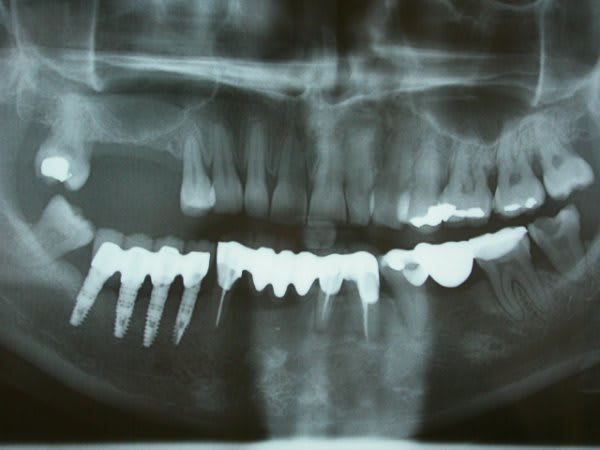

Patiente nouvelle. 38 ans. consulte pour douleur moyenne et gonflement léger au niveau de la 34. A la percussion, la 34 est la seule à réagir de façon modérée.

Je ne suis pas sûre que la 34 ait induit cette infection mais alors ??

que dit la vitalité de la 36 (37?)...la zone est pas bien "claire" sous le pontique...

Plus simplement,mastication unilatérale,( je doute de l'efficacité des implants à ce niveau...), équilibration du bridge ??? ( axe des forces de mastication sur l'inlay?) , destruction ligamentaire, envahissement bactérien...

Tu as raison, les implants ne servent à rien. Je pense que le bridge antérieur subit trop de forces masticatoires et que ses jours sont comptés.

Faut lui dire de changer sa méthode de brossage...Elle a de superbes mylolyses (ou régler le problème de bruxisme si bruxisme il y a ). :))

Oh non Lulu pas de prise de tête sur ce coup la, quand tu regardes le premier pano 34 était sans doute contaminée, une Chompret l'hirondelle ne fait pas le printemps ....